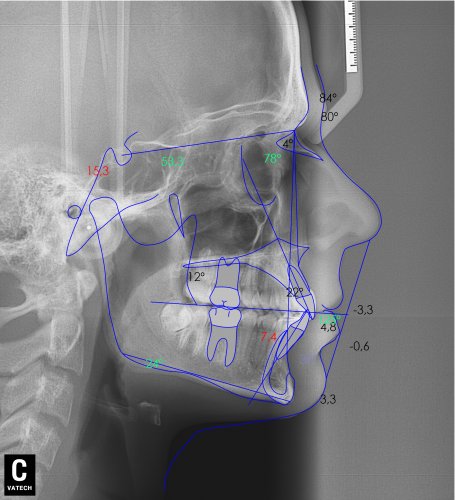

Paciente de 14 años, acude a nuestra consulta por dientes superiores proclinados hacia delante y apiñamiento. El paciente presenta una full clase 2, sobremordida y dientes inferiores proclinados. Decidimos colocarle brackets Damon y microtornillos en maxilar superior para distalizar las muelas. La duración del tratamiento fue de 24meses, y ahora lleva 1 año de contención. El paciente se pone la férula Essix superior 1noche/2 y la de abajo 1noche/semana para mantener.